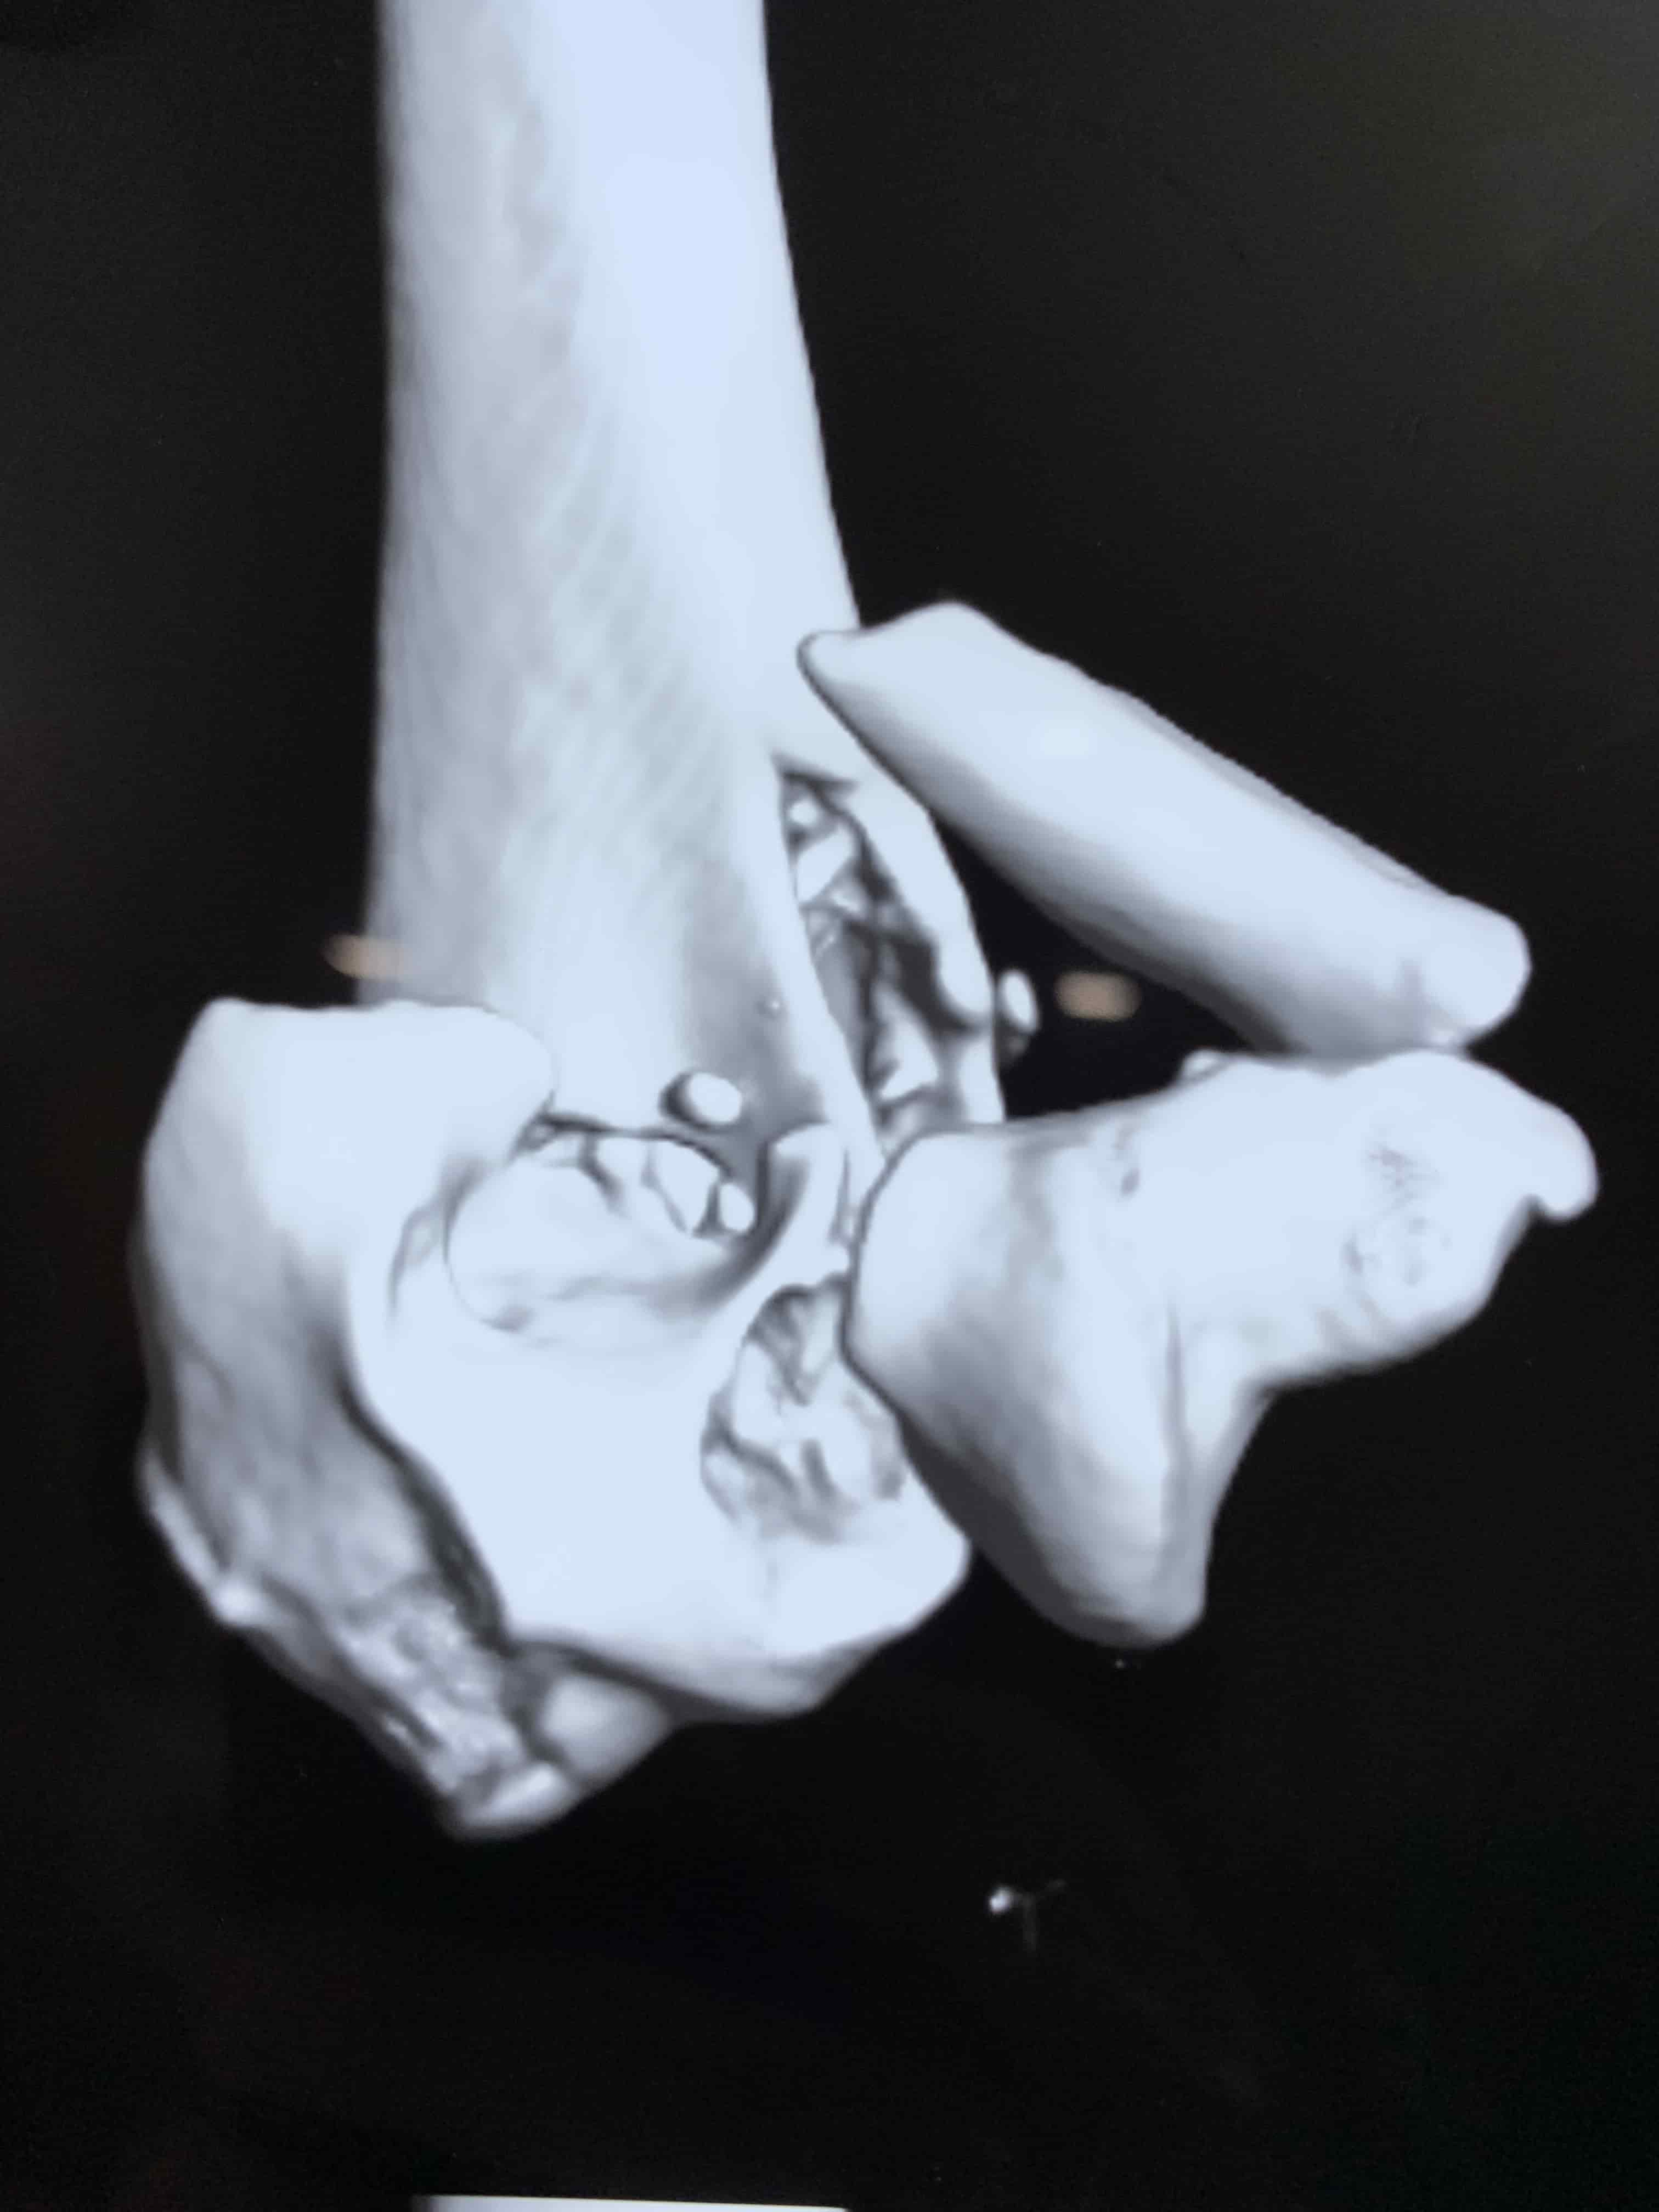

Complex Distal Humerus Comminuted Fracture

Complex Distal Humerus Comminuted Fracture

Complex Distal Humerus Comminuted Fracture

Complex Distal Humerus Comminuted Fracture

Complex Distal Humerus Comminuted Fracture

Complex Distal Humerus Comminuted Fracture

Complex Distal Humerus Comminuted Fracture

Complex Distal Humerus Comminuted Fracture

Complex Distal Humerus Comminuted Fracture

Complex Distal Humerus Comminuted Fracture

Complex Distal Humerus Comminuted Fracture

Complex Distal Humerus Comminuted Fracture

Complex Distal Humerus Comminuted Fracture

Complex Distal Humerus Comminuted Fracture